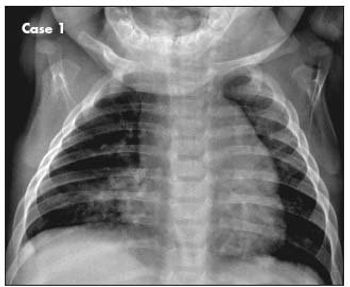

A 6-month-old boy with 1-week history of dry cough that worsened at night. He had been wheezing off and on for the past month and had visited the emergency department on one occasion.

A 5-year-old boy with a history of allergies and asthma presents with fever (temperature of 40°C [104°F]), headache, cough, vomiting, and diffuse pain in and around the chest area on the right side. The patient has never traveled and has no sick contacts. A chest radiograph is obtained (A).